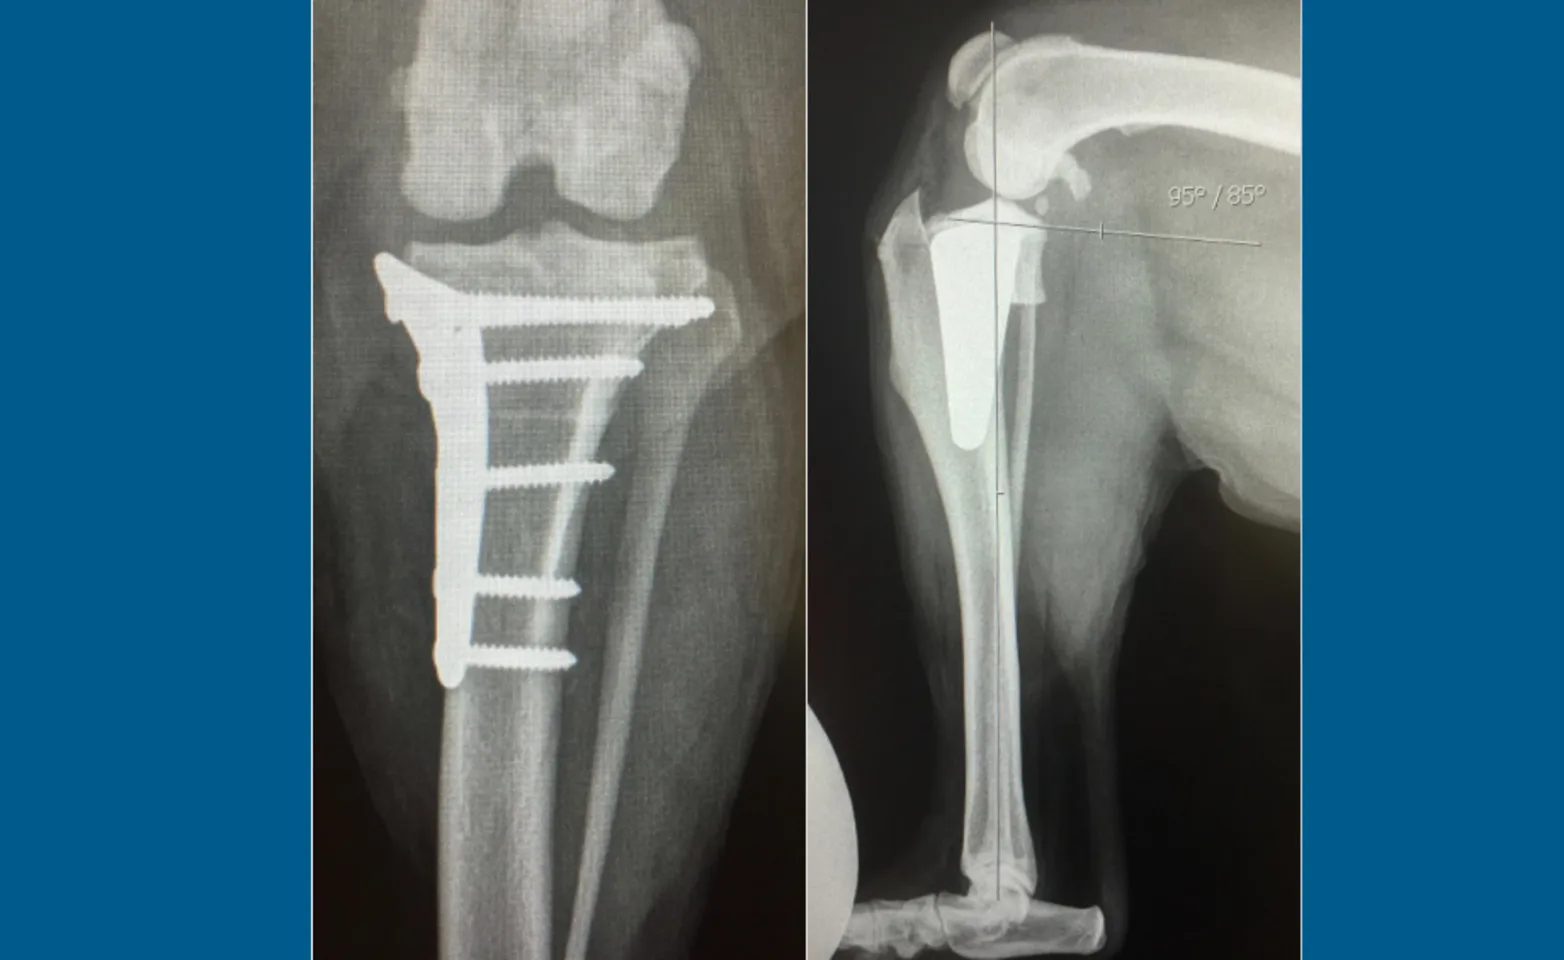

Tibial Plateau Leveling Osteotomy (TPLO)

The tibial plateau levelling osteotomy (TPLO) eliminates the need for the cruciate ligament by levelling the surface of the tibia (the bone below the knee joint) without disturbing the cartilage. A semicircular, full thickness cut in the tibia is performed and the piece is rotated so that the surface is close to the perpendicular to the tibia. The bone is then stabilized with a bone plate and screws. The outcome following the TPLO is characterized by the early return to weight-bearing function and durable, lifelong repair. The prognosis is good to excellent, giving the best chance for resumption of normal activities for dogs with an active or working lifestyle including those with other concurrent orthopedic problems